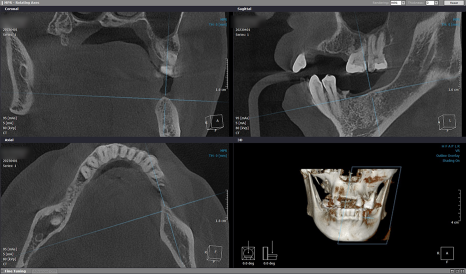

본격적인 치료 전,

픽스처를 심기 위한

치조골 위치를 정확히 파악하기 위해

3D-CT 촬영을 했으며

음식을 씹는 데 불편함이 없으시도록

좌측부터 인공치를 만들기로 했습니다.

환자분 뼈 상태의 해부학적 구조를

면밀하게 파악한 다음

잇몸뼈 높이와 폭, 각도 등을 고려해서

좌측부터 인공 치근을 심었습니다.